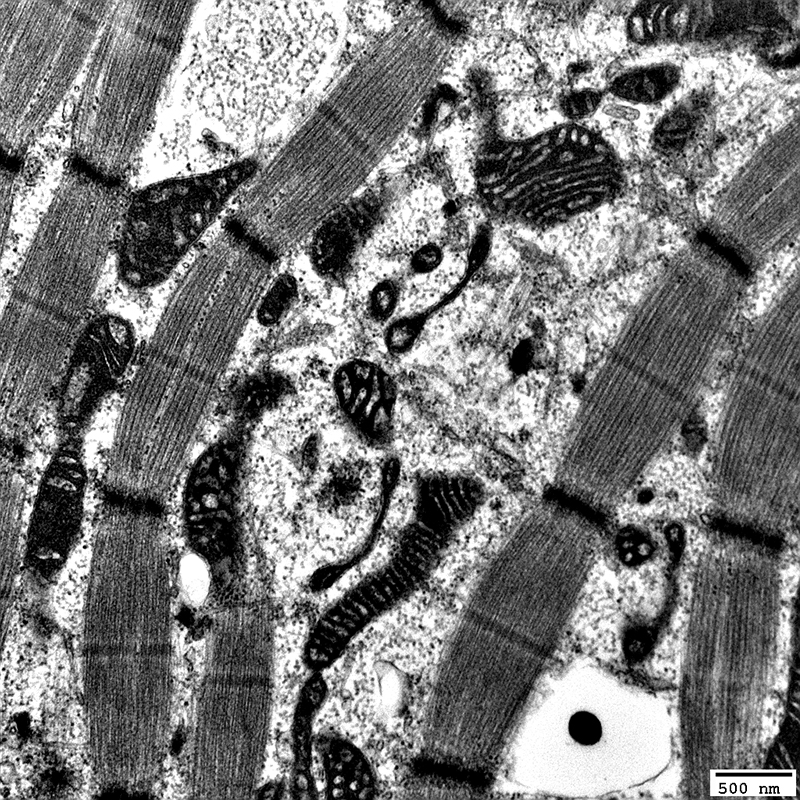

Twinkle: Muscle Ultrastructure

Mitochondrial Proliferation

From: R Schmidt; C Cai

Mitochondria: Subsarcolemmal accumulations

Many mitochondria are abnormal: Large; Long; Dark-stained